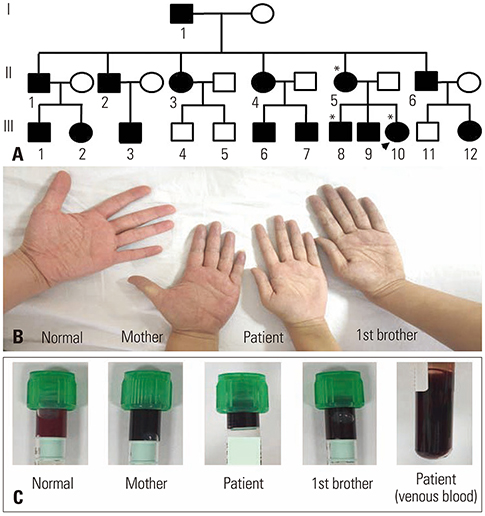

clubbed fingers – also known as clubbing is a finger deformity associated with heart or lungs diseases involving constant low oxygen levels. Here, the angle of nail bed gets distorted, fingernails enlarge and get really curvy. The most common cause of clubbed finger is lung cancer however it can also be caused by heart defects, heart/lung infections, celiac disease, cirrhosis etc.